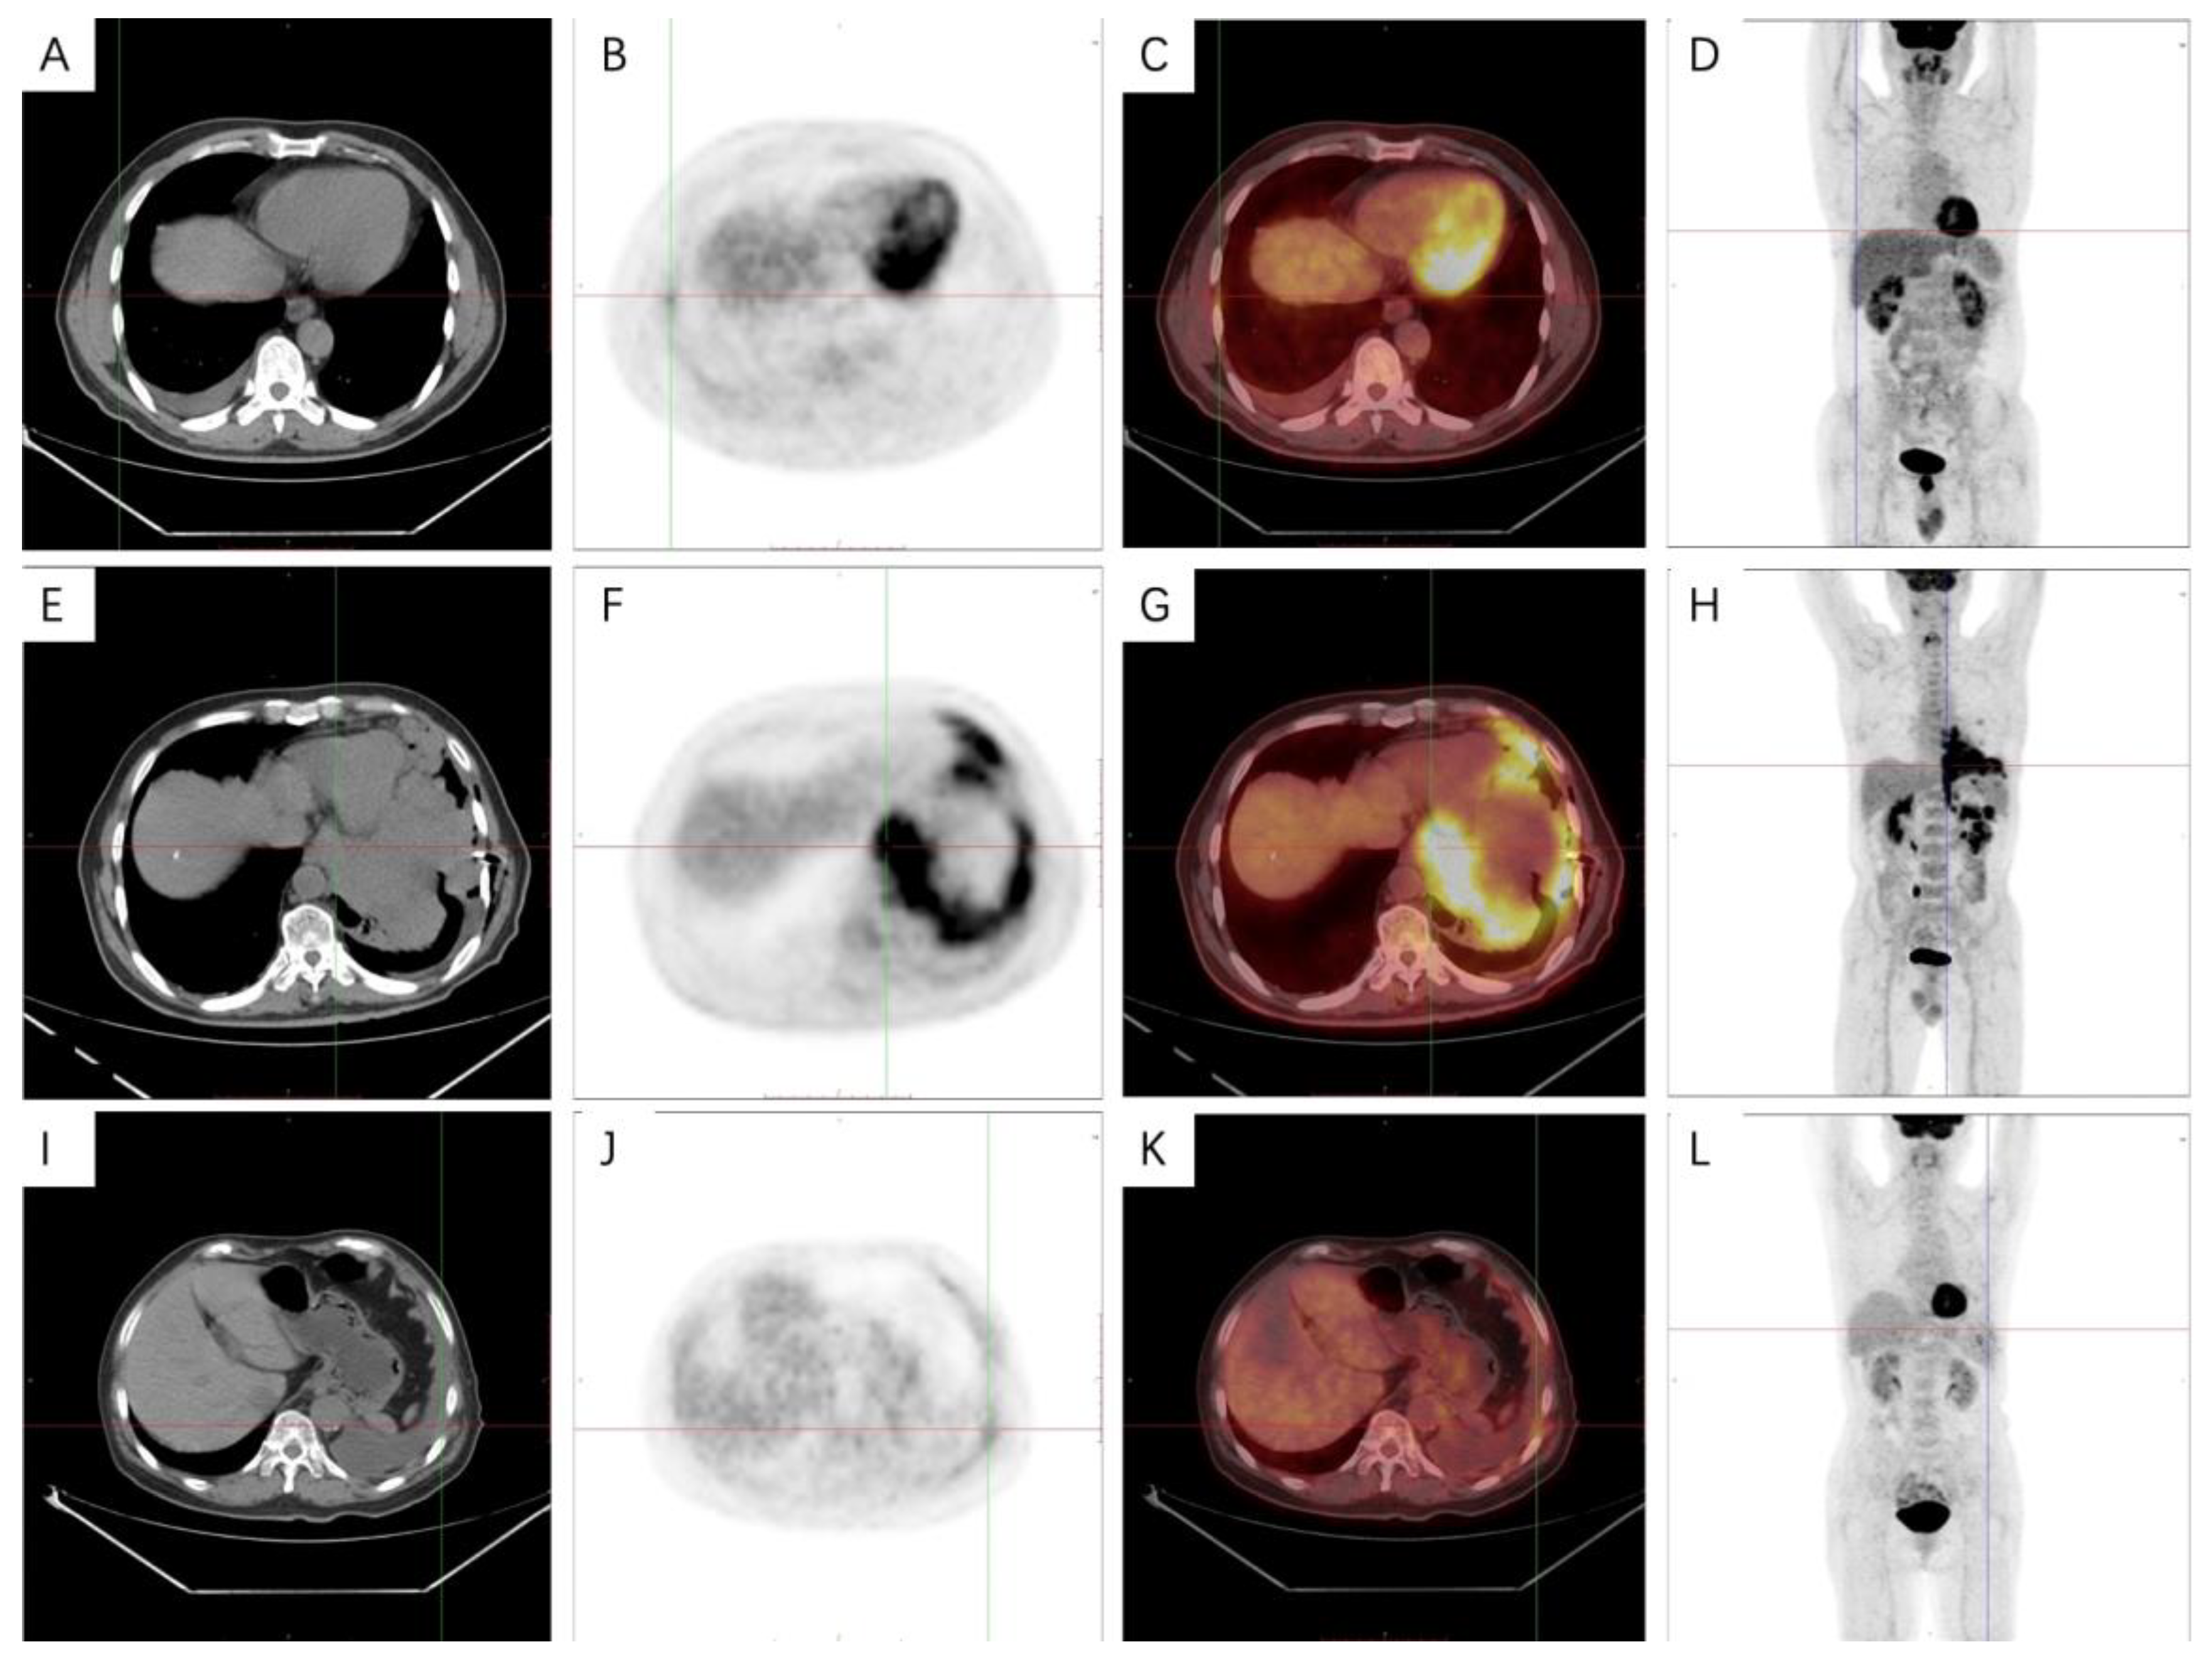

3.5. PET-CT Metabolic Characteristics

4.4. PET-CT Metabolic Features of Malignant Pleural Mesothelioma